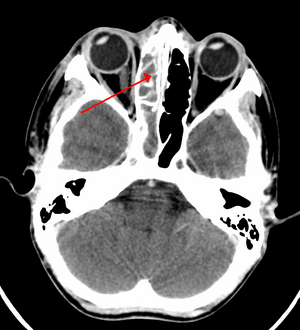

A CT scan showing sinusitis of the ethmoid sinus | |